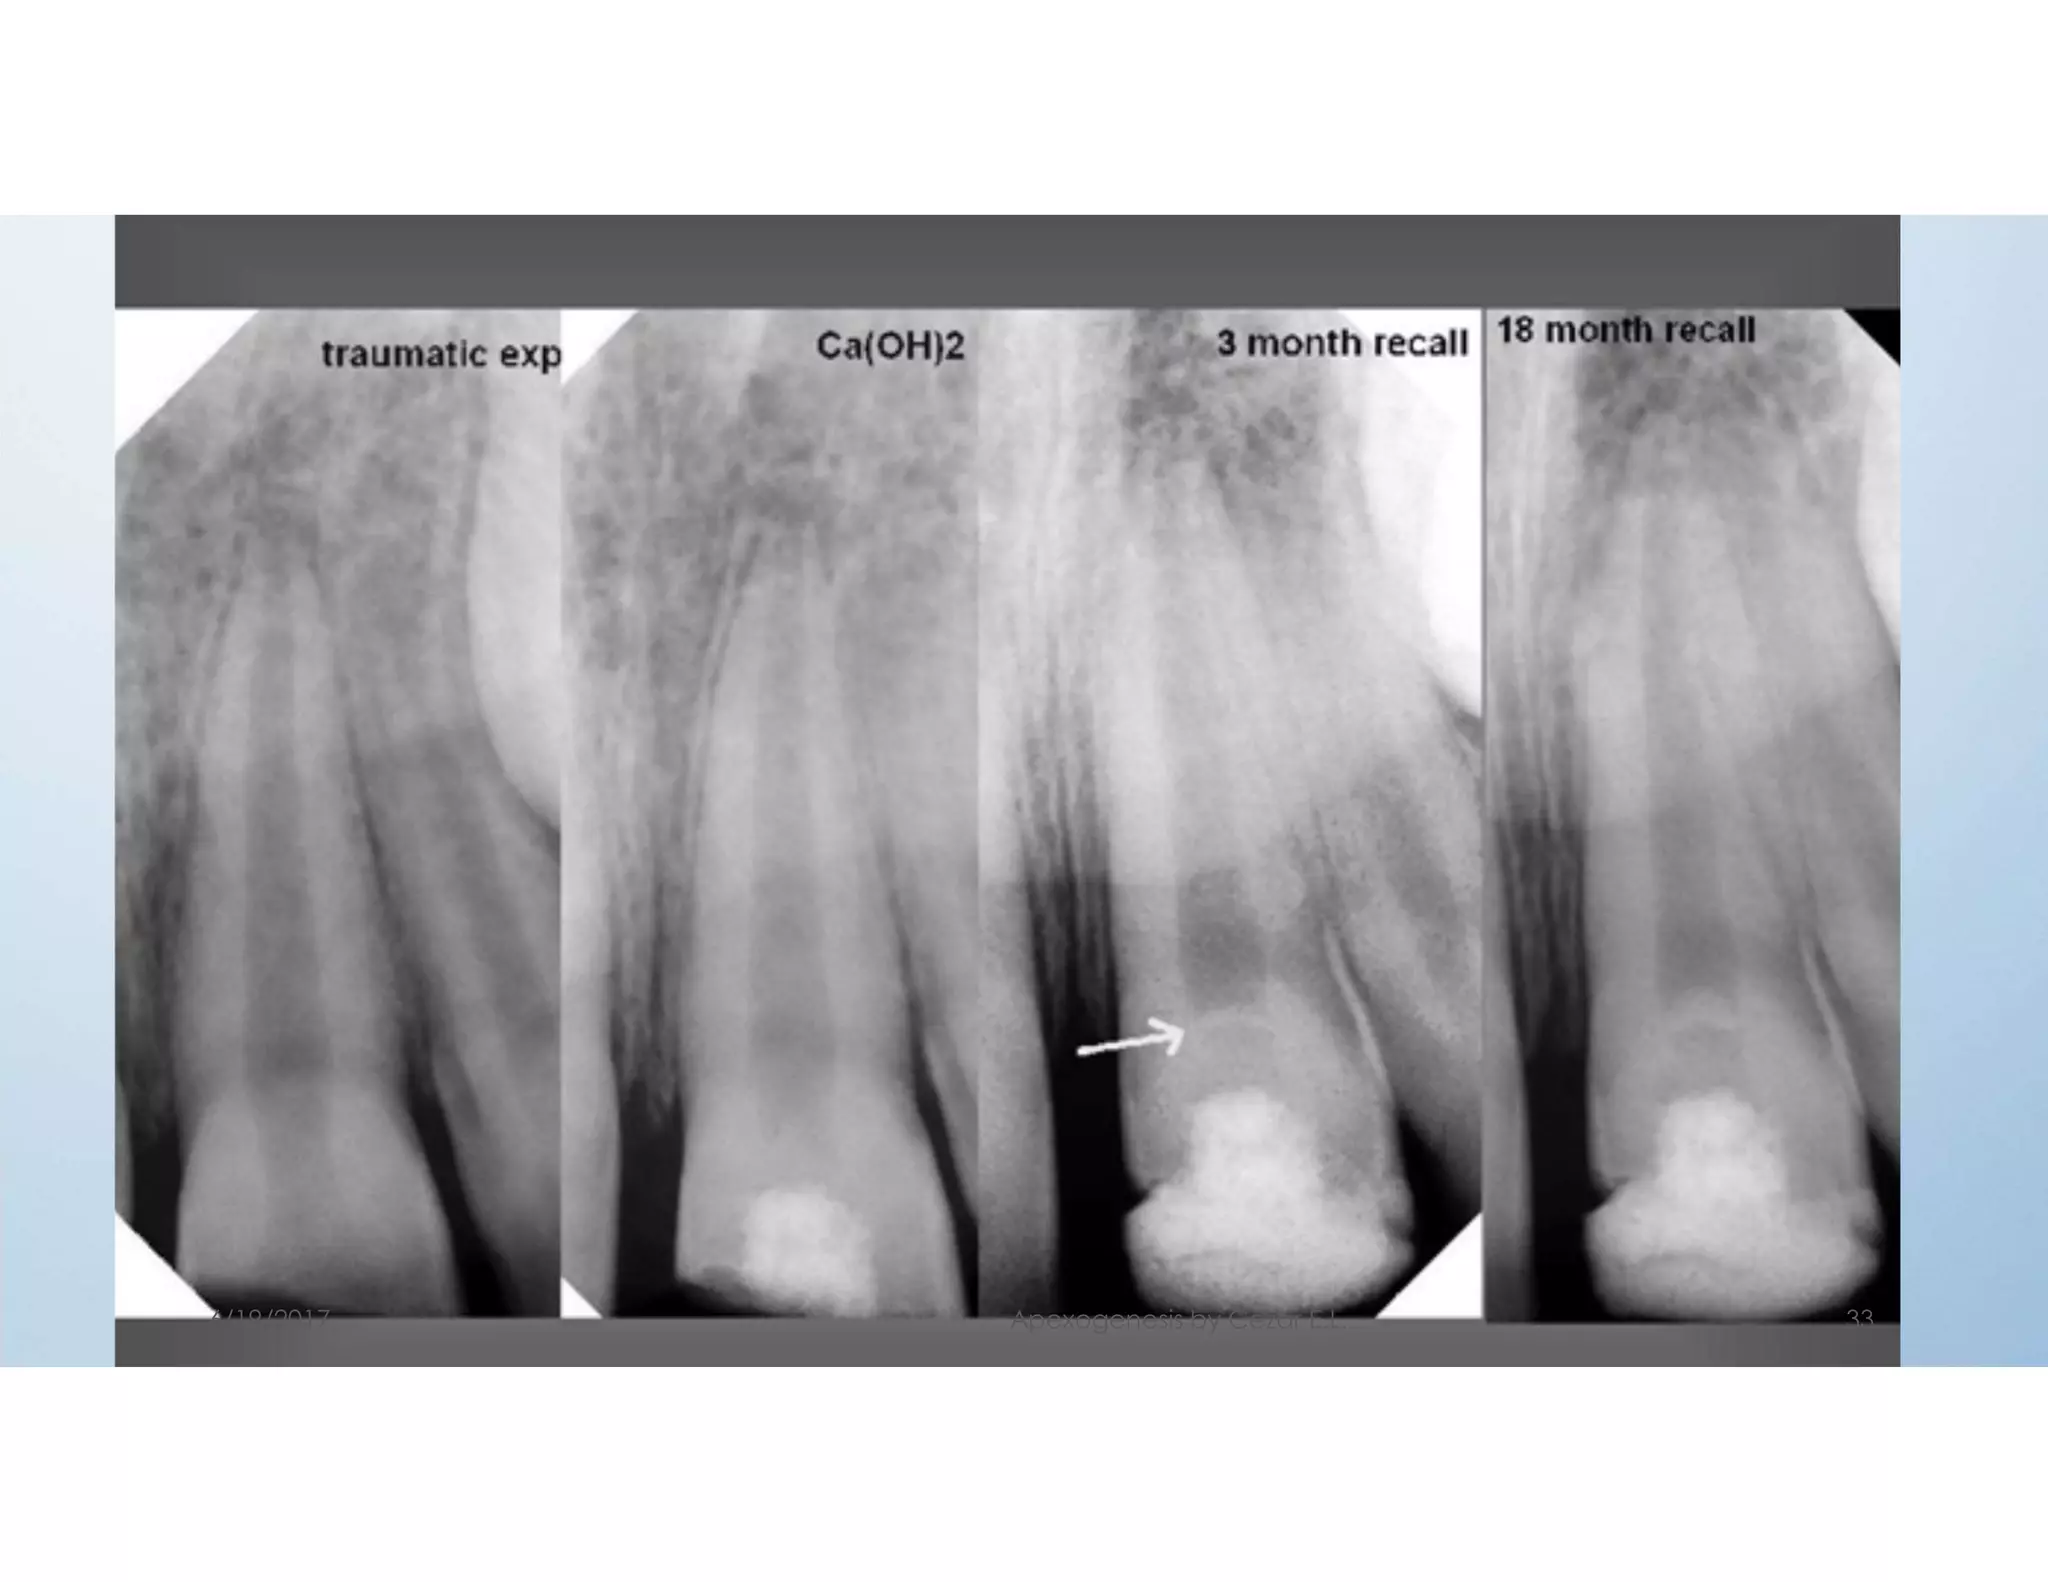

Treatment outcome

- The hard tissue barrier over the pulp may be

observed as early as 6 weeks.

- The apexogenesis or completion of root may

take unto 2-4 years.

When is pulpotomy considered successful:

1- Clinically the tooth should be asymptomatic

without tenderness and mobility.

6/19/2017 Apexogenesis by Cezar E.L. 31

2- The periodontium should remain healthy

without pockets or sinus.

3- The tooth should respond normally to the pulp

vitality tests.

4- Radiographically a calcific barrier should be seen .

5- There should not be external or internal resorption.

6- The root formation should have been completed

with the apex closed.